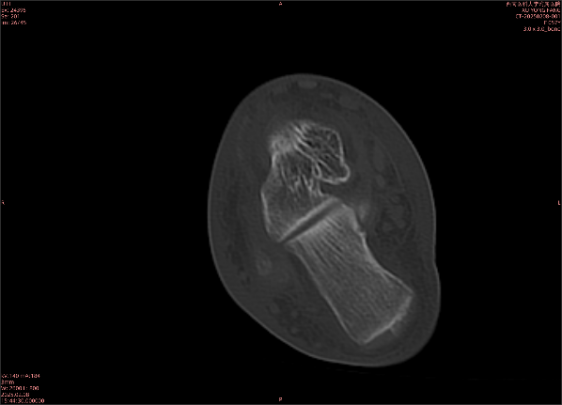

舉例圖像

圖2

專業(yè)解釋看不懂沒關(guān)系,大家看圖1和圖2就可以了,這是同一個患者跟骨的磁共振和CT圖像,圖1的紅色箭頭指示的黑線就是磁共振圖像顯示的骨折線,一目了然。而對比圖2的CT圖像上并未顯示異常。